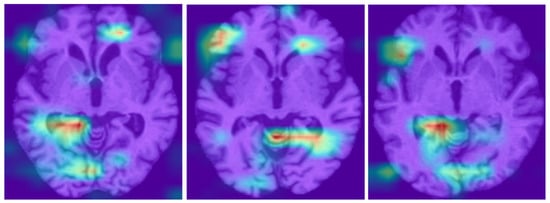

Preliminary Study on Image-Finding Generation and Classification of Lung Nodules in Chest CT Images Using Vision–Language Models

Computers 2025, 14(11), 489; https://doi.org/10.3390/computers14110489 - 9 Nov 2025

In the diagnosis of lung cancer, imaging findings of lung nodules are essential for benign and malignant classifications. Although numerous studies have investigated the classification of lung nodules, no method has been proposed for obtaining detailed imaging findings. This study aimed to develop

In the diagnosis of lung cancer, imaging findings of lung nodules are essential for benign and malignant classifications. Although numerous studies have investigated the classification of lung nodules, no method has been proposed for obtaining detailed imaging findings. This study aimed to develop a novel method for generating image findings and classifying benign and malignant nodules in chest computed tomography (CT) images using vision–language models. In this study, we collected chest CT images of 77 patients diagnosed with either benign or malignant tumors at Fujita Health University Hospital. For these images, we cropped the regions of interest around the nodules, and a pulmonologist provided the corresponding image findings. We used vision–language models for image captioning to generate image findings. The findings generated by these two models were grammatically correct, with no deviations in notation, as expected from the image findings. Moreover, the descriptions of benign and malignant characteristics were accurately obtained. The bootstrapping language–image pretraining (BLIP) base model achieved an accuracy of 79.2% in classifying nodules, and the bilingual evaluation understudy-4 score for agreement with physician findings was 0.561. These results suggest that the proposed method may be effective for classifying and generating lung nodule findings.